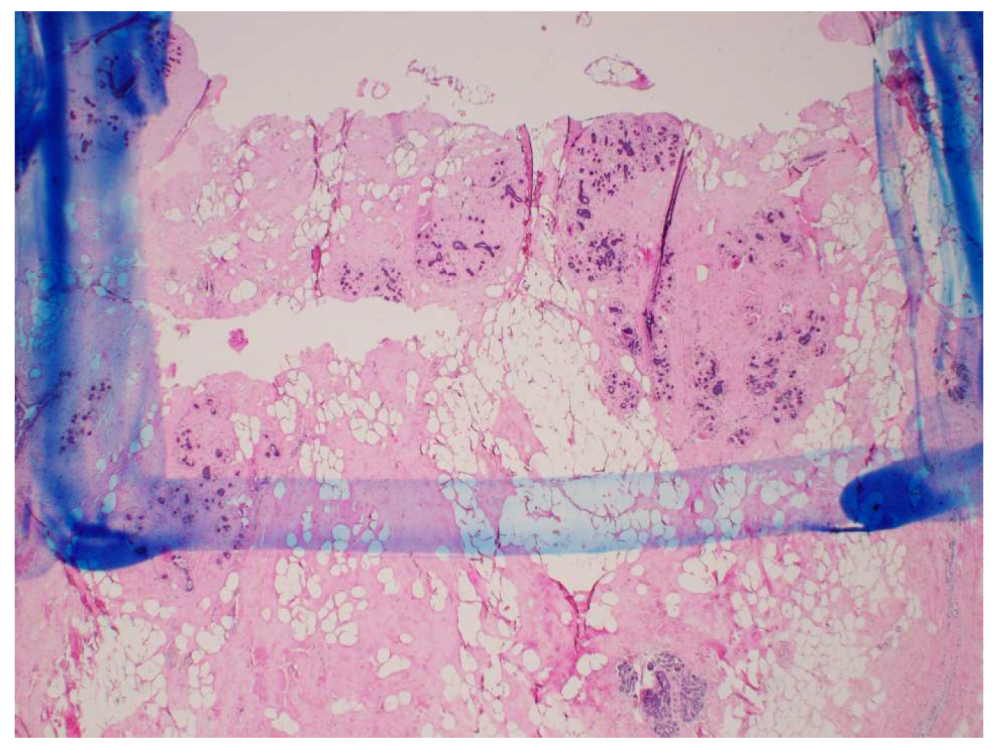

A small piece of tissue at each of the measurement locations was removed and sent for histological analysis after the dielectric spectroscopy measurements were completed and the location of the measurements was inked. The analysis consisted of evaluating the tissue composition (proportion of adipose and fibroglandular tissue) and the damage observed in the sample (proportion of fibroglandular cells that showed evidence of thermal damage). Thermal damage was described by cautery-like effects and nuclear disruptions in epithelial cells. The volume analyzed by the pathologist consisted of an area extending 1.5 mm into the tissue from the surface, with a width of 5 mm. This region was chosen to correspond to the sensing volume of the 2.2 mm diameter open-ended coaxial probe used for the dielectric measurements. Figure 6 shows a schematic of the histology slide that was obtained from the probe measurement location (ink spot), as well as the specific region that was evaluated within the sample. Figure 7 shows an example of one of the actual histology slides, with the delimitation drawn by the pathologist to mark the 1.5 mm by 5 mm analysis region. Of the histology slides that were taken at four locations in the fourteen specimens, four were excluded from our results and analysis, since they did not correspond to the standard locations shown in the schematic in Figure 3.

Figure 7. 2X magnification of histology slide showing the 1.5-mm by 5.0-mm analysis region.

Figure 10. 20X magnification of histology slide showing intact glandular lobule (a) and evidence of thermal damage in glandular lobule (b).